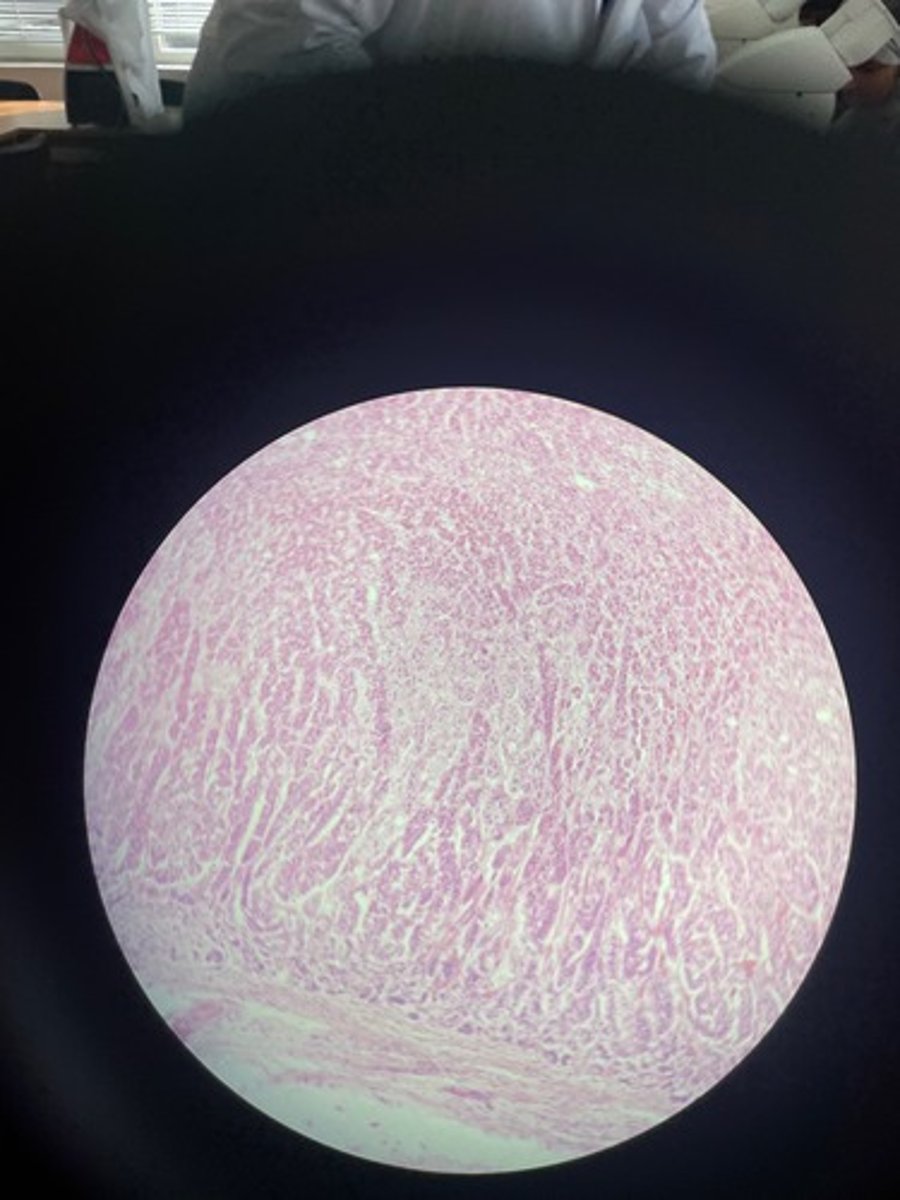

Adrenal gland HE

Adrenal gland HE

Adrenal gland HE

Adrenal gland HE

Adrenal gland

Adrenal gland HE